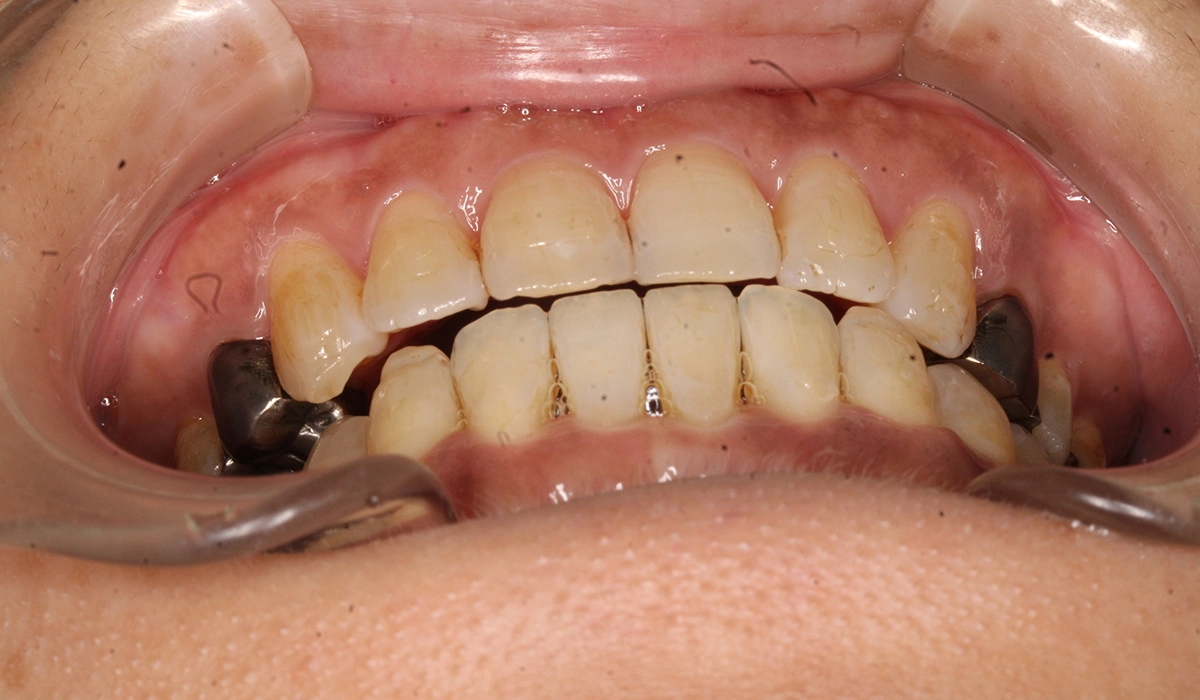

術前:正面